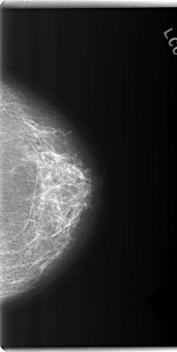

C_0202_1.LEFT_MLO

LEFT_MLO LINES 5976 PIXELS_PER_LINE 2888 BITS_PER_PIXEL 12 RESOLUTION 50 NON_OVERLAY